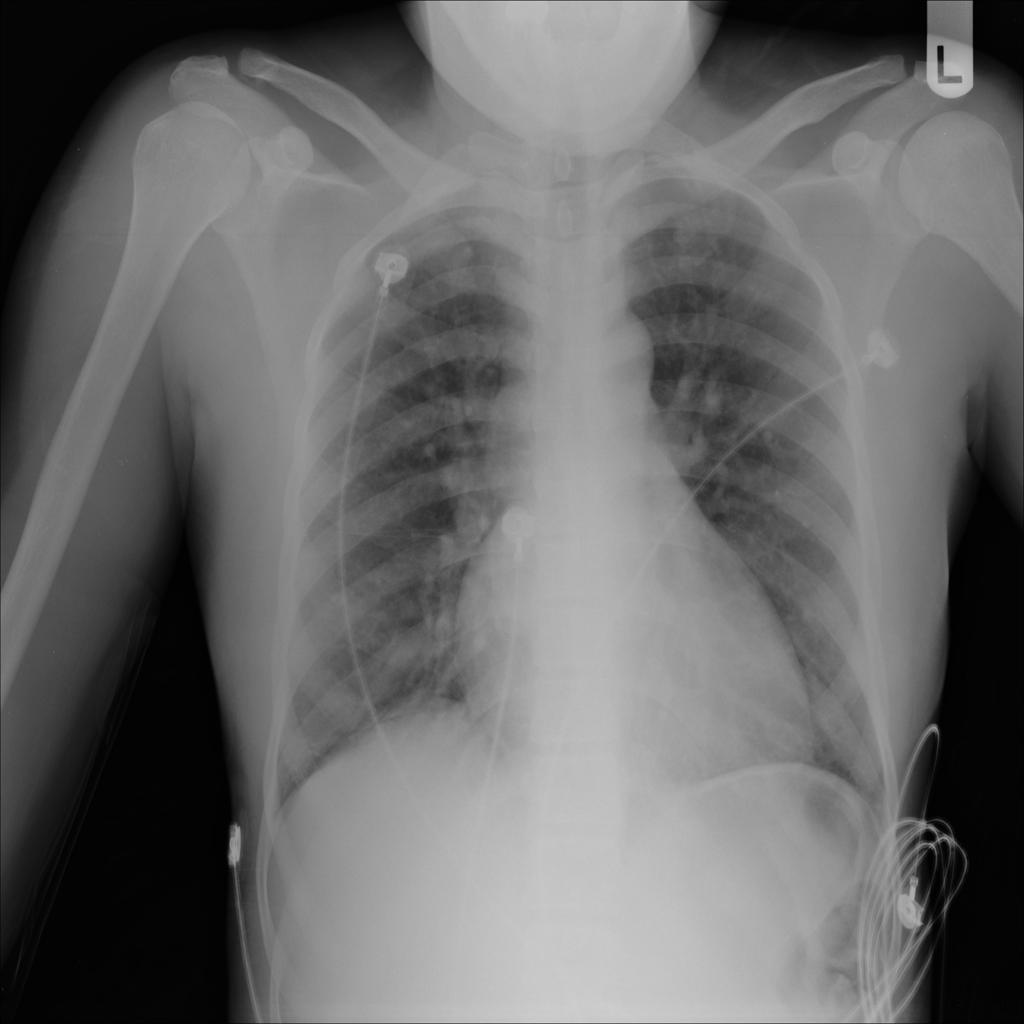

PAT-5B86 · IMG-009Edema

PAT-5B86 · IMG-009

PA